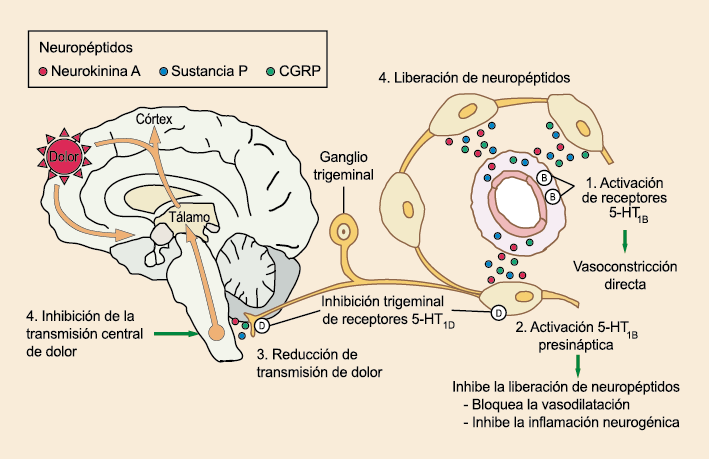

La comprensión de la biología de la migraña a través de una cuidadosa investigación de laboratorio ha llevado al desarrollo de las principales clases de tratamientos: triptanos, agonistas del receptor de serotonina 5-HT1B/1D; gepants, antagonistas del receptor del péptido relacionado con el gen de la calcitonina (CGRP); ditanes, agonistas del receptor 5-HT1F, CGRP anticuerpos monoclonales; moduladores de mGlu5, sin olvidar el efecto ya demostrado por parte de los bloqueantes de los canales de calcio (flunarizina) y de los neuromoduladores; bien se trate de topiramato (Inhibe la acción de la anhidrasa carbónica, bloquea los canales del sodio, aumenta las corrientes de cloro mediadas por GABA, activa las corrientes hiperpolarizantes del K+ e inhibe la activación de receptores a ácido glutámico tipo AMPA), valproato de sodio (Inhibe las enzimas de degradación del GABA y puede aumentar su síntesis, además de tener un papel inhibidor de la transmisión excitatoria de ciertos aminoácidos, entre ellos el glutámico y reducir el umbral de conductancia del calcio y el potasio) y de los antidepresivos de diversas clases como la amitriptilina (antidepresivo tricíclico que impide la recaptación y la inactivación de la noradrenalina y la serotonina en las terminaciones nerviosas) y venlafaxina (inhibe principalmente la recaptación de serotonina y en menor grado de noradrenalina, en la membrana presináptica neuronal, potenciando la neurotransmisión a nivel del sistema nervioso central). El propanolol tiene un efecto antagonista de los adrenoceptores β1 en las neuronas del núcleo VPM (postero medial ventral) del tálamo que responden a la entrada nociceptiva trigeminovascular. Se ha demostrado que el propanolol previene los cambios en el comportamiento y el flujo sanguíneo cerebral inducido por la depresión cortical propagada, además de bloquear los canales de sodio del cerebro(103), modulación del sistema catecolaminérgico central(104) probablemente a través de receptores β-adrenérgicos centrales e interacción cruzada con receptores de serotonina(105) (Figura 4).

Los terminales axónicos de las fibras nerviosas nociceptivas que inervan la duramadre contienen neuropéptidos vasoactivos CGRP, sustancia P, neurocinina A y péptido activador de la adenilato ciclasa pituitaria (PACAP)(25) (Figuras 13 y 14), que se cree que son liberados tras la estimulación que causa la vasodilatación de los vasos durales y piales(26) (Figura 15).

La activación del sistema trigeminovascular da como resultado la liberación de varios neuropéptidos basados en las inervaciones simpática, parasimpática y sensorial de la vasculatura craneal, que se resumen en la figura 23.

La inervación simpática se caracteriza por NPY y norepinefrina(52), ambos de los cuales son vasoconstrictores, mientras que las fibras parasimpáticas se caracterizan por VIP y PACAP, que se encuentran entre los vasodilatadores más potentes(24).

Las inervaciones sensoriales se caracterizan por la sustancia P, CGRP y PACAP (53).

Posteriormente diversos estudios demostraron que la infusión de 5-HT podría abortar tanto la cefalea inducida por reserpina(55) como la espontánea(56). En respuesta a estos estudios, el sistema del receptor 5-HT ganó mucha atención, lo que culminó con el descubrimiento de los triptanos, la serotonina y los agonistas del receptor 5-HT1B/1D(57). Todos exceptuando el 5-HT3 (canal iónico controlado por ligando) son receptores acoplados a proteína G. Si bien los triptanos se clasifican como agonistas de los receptores 5-HT1B/1D, la mayoría también activa en menor medida los receptores 5-HT1A, 5-HT1E o 5-HT1F(58). Originalmente, los triptanos se desarrollaron para actuar sobre la vasculatura craneal, una idea apoyada por sus claras acciones vasoconstrictoras(59) (Figura 25) y la expresión preferencial del receptor 5-HT1B en los vasos craneales más que en los periféricos(60).

Un mecanismo neural de los triptanos en las terminaciones del nervio trigémino periférico podría inhibir la liberación de neuropéptidos proinflamatorios y la vasodilatación dural neurogénica(63), lo cual era consistente con el tema en desarrollo de la migraña como una enfermedad neurovascular. (Figuras 26 y 27)

En la figura 28 se muestra un resumen de los fármacos y sus mecanismos de acción en el contexto del sistema trigémino vascular.

A pesar de la clara farmacología de los triptanos en el tratamiento de la migraña, su uso es limitado en pacientes con factores de riesgo cardíaco(61), lo que obliga a dirigirse a receptores que carecen de acción vasoconstrictora. Una de esas dianas es el receptor 5-HT1F, que es activado hasta cierto punto por algunos triptanos, como el naratriptán y no por otros, como el rizatriptán(62). (Tabla 2)